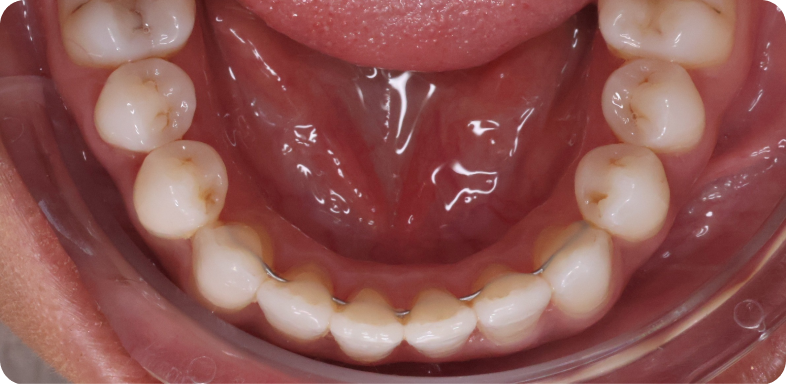

- des fils de contention collés sur la face interne des incisives et canines, à la mandibule et au maxillaire lorsque cela est possible, à conserver le plus longtemps possible ;

Cas cliniques